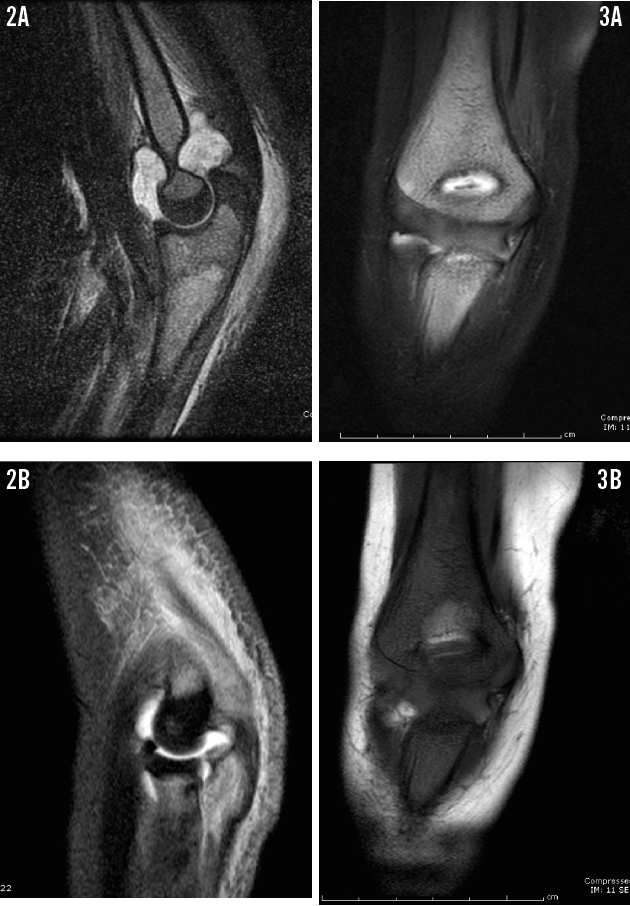

Over the next month, now 2 months before the current presentation, his pain continued. He was admitted for left elbow pain and significant joint swelling concerning for a septic joint. Joint aspirate testing revealed a white blood cell (WBC) count of 111,670/µL (96% neutrophils) and negative culture results. T2-weighted magnetic resonance imaging (MRI) of the left elbow showed increased marrow signal at the proximal radius, ulna, and metaphysis of the medial humeral condyle (Figure 2), which prompted a diagnosis of septic left elbow with osteomyelitis. However, given the boy’s history of recurrent joint pain and his recent fracture, a diagnosis of chronic recurrent multifocal osteomyelitis (CRMO) also was strongly considered. MRI of the right elbow also was performed at that time, but with limited results due to motion artifact (Figure 3). The patient was started on intravenous clindamycin and underwent irrigation and debridement of the joint. He was discharged home on postoperative day 8 after placement of a central venous catheter for home antibiotic infusion.

ALL can present with a number of radiographic changes. The numerous radiographs taken of our patient’s extremities showed none of the commonly described bony changes. These typical changes include metaphyseal bands, periosteal reaction, osteopenia, lytic lesions, sclerosis, pathologic fractures, and effusions. Classically, leukemic marrow presents as increased brightness on fat-suppressed T2-weighted MRI.12 These changes can be seen in both ALL and osteomyelitis, which confounded the initial diagnosis in our patient.